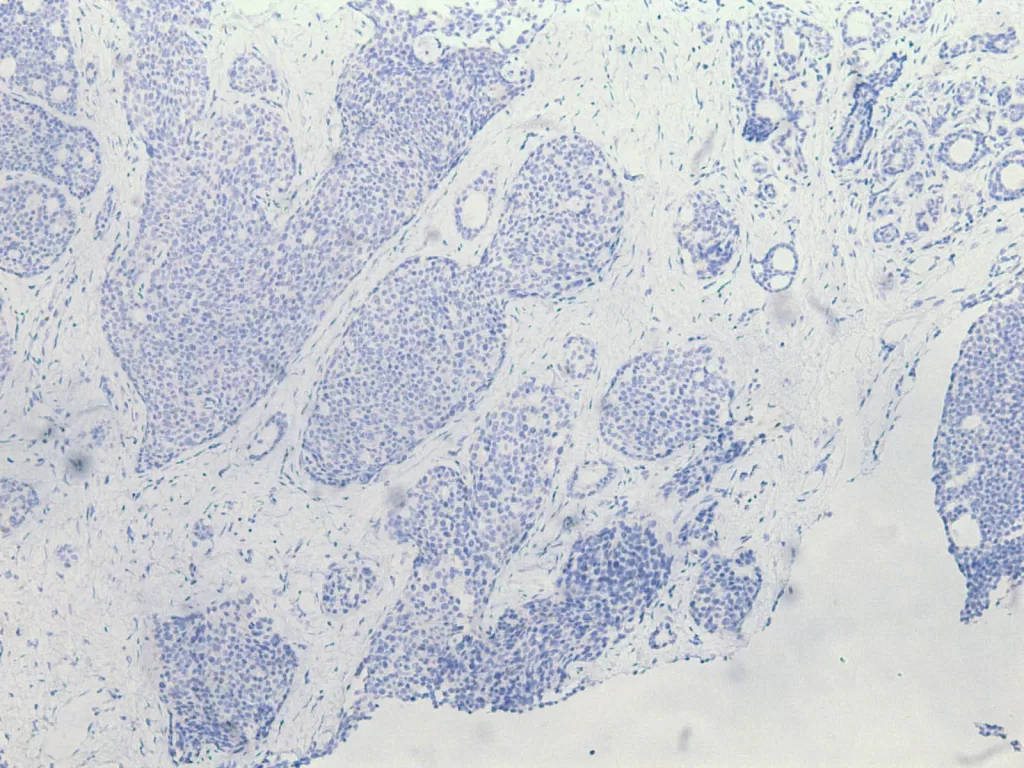

使用標靶藥物如 Trastuzumab(赫賽汀)、Pertuzumab(帕妥珠單抗)、T-DM1(Kadcyla)。這些標靶藥可以針對癌細胞,幫助失控的身體踩下煞車。 - 三陰性乳癌(ER– / PR– / Her2–)

主要以化療或免疫治療為主:Paclitaxel、Carboplatin、Pembrolizumab(Keytruda)。雖然沒有特定的「開關」可以關掉,但醫學仍在為這些叛逆的細胞尋找新的治療方式。

當妳做完乳房攝影或超音波,那一小片被切下的組織會進入顯微鏡的世界。病理醫師在那裡看見平常看不見的部分,那些色彩、結構與節奏,試著從中解讀身體的語言。最後的病理報告不僅僅是診斷,更是傳達了妳的身體在說什麼、帶來了怎麼樣的希望。